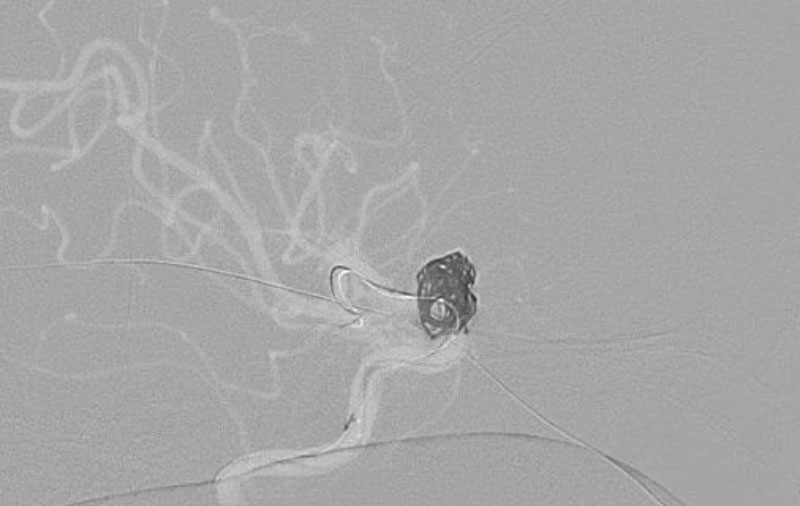

No.1596 手術前

No.1596 手術中